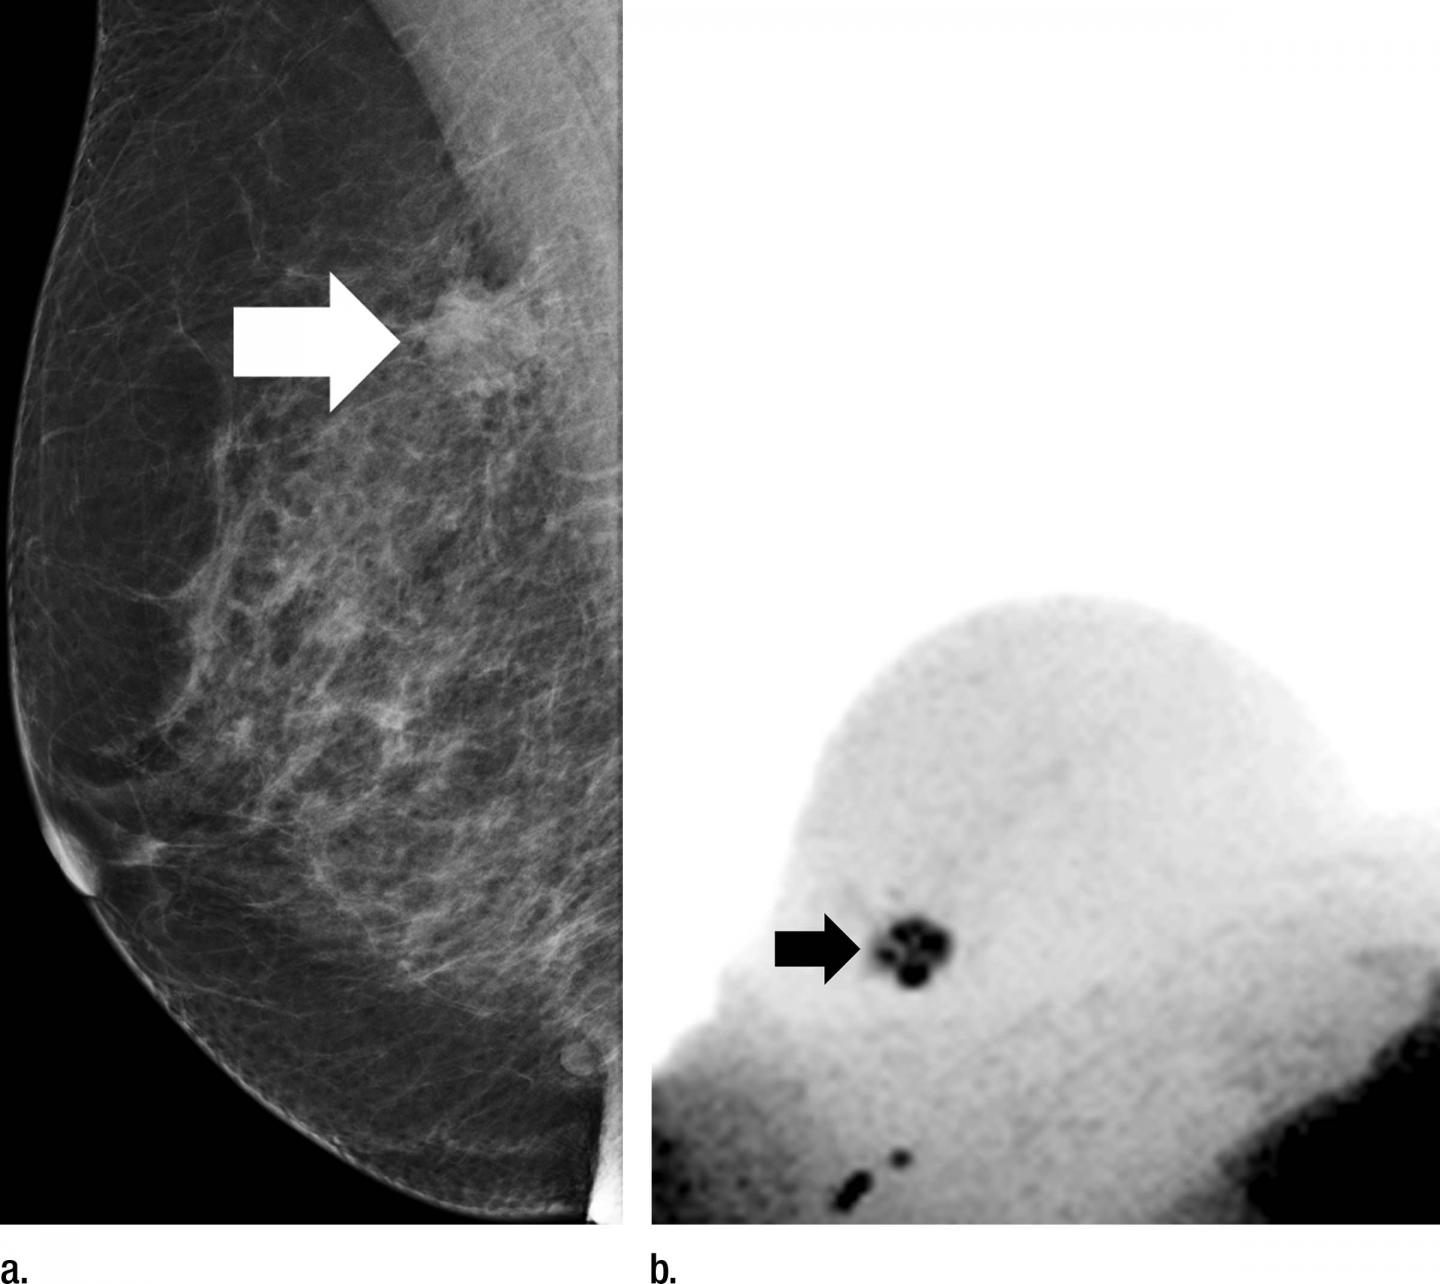

Screening programs with conventional X-ray mammography have been shown to reduce breast cancer deaths; however, conventional mammography has a high false-positive rate, leading to many unnecessary biopsies. MR imaging could be a useful adjunct to mammography, but the examinations can be time-consuming and commonly require the injection of a contrast agent, which carries its own cost and potential complications.

For the new study, researchers in Germany evaluated an abbreviated MR breast imaging protocol that requires no contrast agent. The protocol uses only two short sequences: the first to show the shape and appearance of the lesion and the second to display its biophysiological properties with diffusion-weighted imaging with background suppression magnetic resonance mammography (DWIBS-MRM), a technique that works by assessing the diffusion, or movement, of water molecules through tissue. Areas of restricted diffusion may indicate malignancy.

The researchers compared DWIBS-MRM to an abbreviated contrast-enhanced MRI and full diagnostic breast MR protocol in 50 women with suspicious screening mammograms and indication for biopsy.